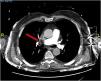

A 76-year-old man was admitted to the emergency department after suffering a syncope. Computed tomography revealed acute bilateral pulmonary embolism (PE), predominantly on the right side (Fig. 1). In the ICU, electrical impedance tomography (EIT) monitoring was started. A ventilation–perfusion (VQ) study revealed a perfusion defect in the right upper lung with preserved ventilation visible as a corresponding high VQ (blue colored) area in the VQ map and a ventilation deficit with preserved perfusion in the dorsal lung appearing as a low VQ (red colored) area (Fig. 2). After conventional clinical management including anticoagulation and PEEP optimization and clinical improvement, both hemodynamic parameters and a new VQ study revealed recovery of the perfusion defect and normalization of VQ matching in all lung regions (Fig. 3). This case illustrates the usefulness of EIT to detect and follow clinical management of severe PE.